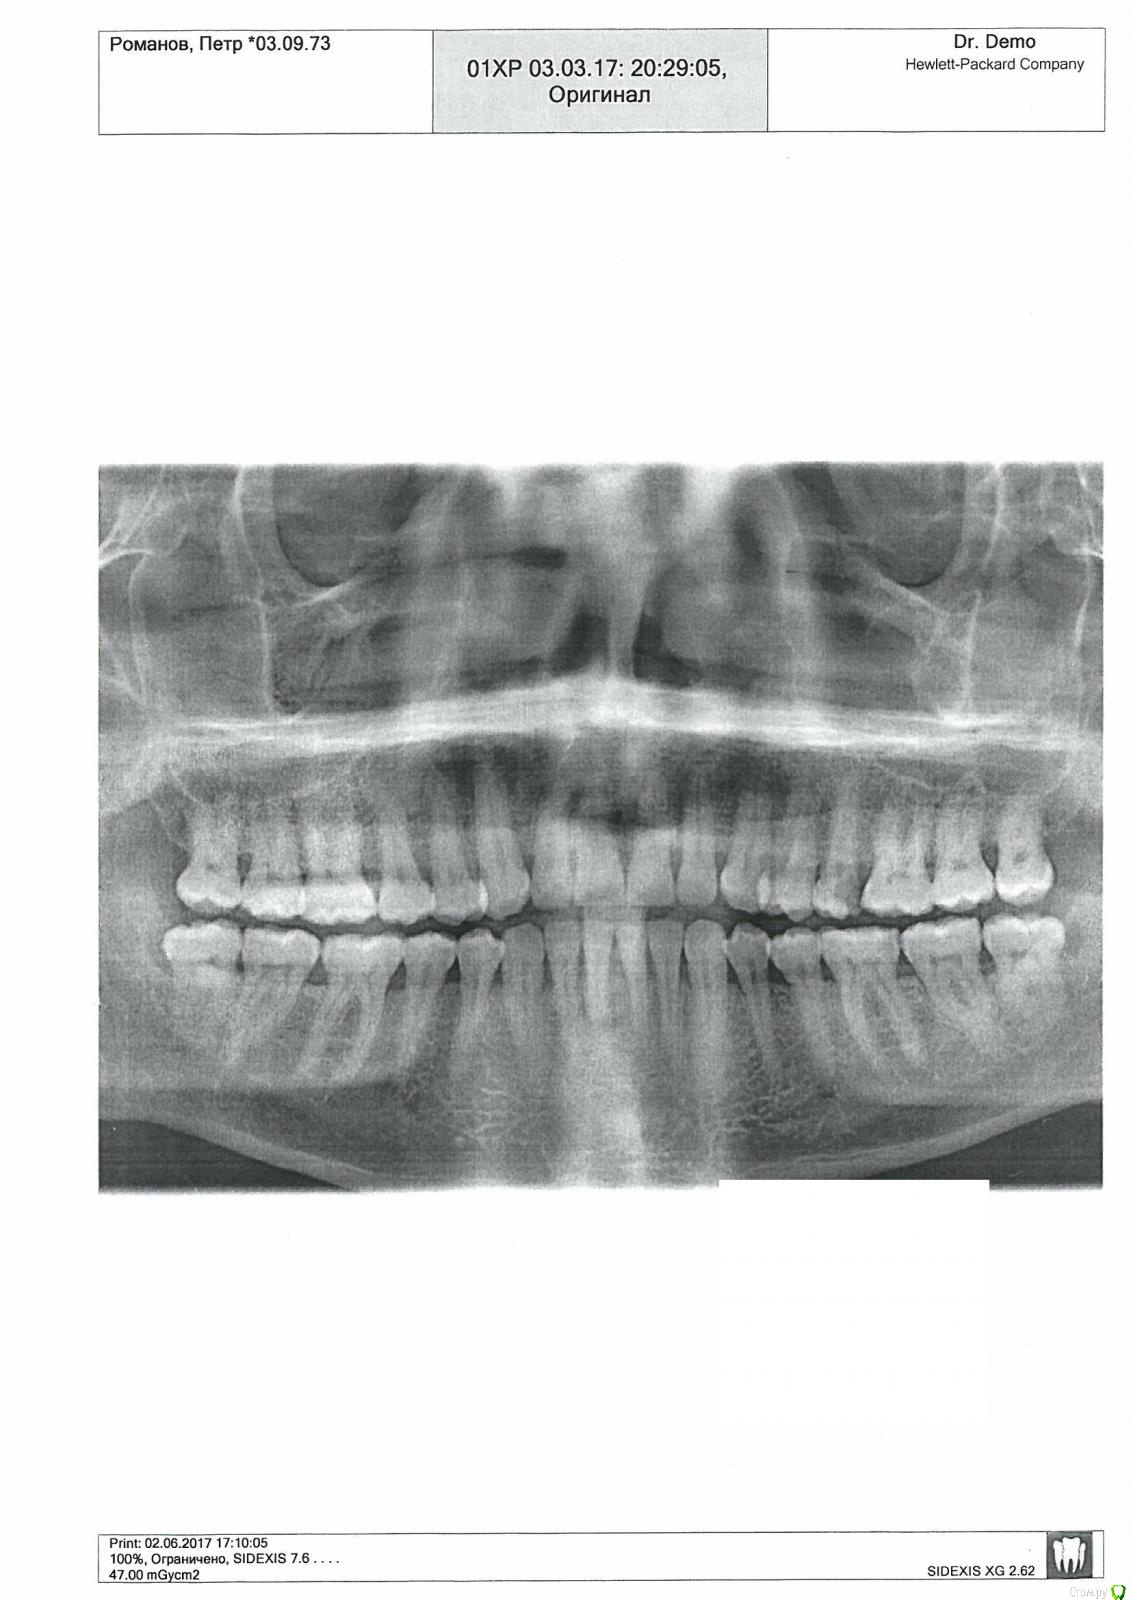

Piter Опубликовано 28 мая, 2018 Поделиться Опубликовано 28 мая, 2018 Добрый день! Хотел бы получить ответ на некоторые вопросы. Получилось так, что до 43 лет я не имел серьезного знакомства со стоматологами, так как всегда веду здоровый образ жизни и самое главное, что у меня не было ни одной пломбы! Обратившись в одну клинику г.Москвы для проверки состояния моих зубов. Я это делаю раз в год и по рекомендации врачей делаю чистку зубов. Хочу заметить, что я не курю. Так вот мне сообщили, что у меня с зубами проблемы и нужно поставить кучу пломб. Я сначала как то подумал, что меня просто пытаются развести, но решил, что наверное пришла пора моим зубам участь временного ремонта. Начав лечение зубов, а лечение проходило более двух месяцев. Я не буду описывать, что мне сделала данная клиника, но через месяц после начала лечения и установки пломб, а так же мне на один зуб установили коронку мне вдруг сообщили, что мне нужно удалить еще 38 и 48 зуб, так как если их не удалить то они могут нанести вред жевательным соседним зубам и тогда у меня будет еще больше проблем! Поверив опытным врачам я пошел на поводу и мне удалили зубы. Не могу описать какие у меня были проблемы, но проблемы есть и сейчас так как жевать очень сложно и по сей день и болят соседние зубы. Я решил пойти со снимком в другую клинику и задать простой вопрос: Правильно ли я сделал, что удалил зубы? Врач сообщил, что согласно снимка необходимости в удалении зубов не было! Я пришел в стоматологию где мне лечили зубы и в письменном виде попросил пояснить мне почему мне удалили здоровые зубы? Через неделю получил ответ:По факту удаления 38 и 48 зубов выявлено следующее: на момент обращения и осмотра пациента, было выявлено хроническое воспалительное изменения костных и мягких тканей, окружающих 38 и 48 зубы в стадии обострения (гноетечения из карманов, подвижность зубов)У меня из за этого возникли вопросы:1. Если имеется гноетечение из карманов зубов № 38,48 требуется ли срочное лечение, а возможно и удаление зубов? 2. Реставрируются, пломбируются ли зубы, устанавливаются коронки на зубы при наличии воспалений, гноетечений?3. Каковы последствия для Пациента если при гноетечении из карманов не лечить зубы более одного месяца?4. По утверждению Клиники зубы № 38,48 были подвижны, а из карманов происходило гноетечение: Мне проводили лечение с 3.03., а только 14.04. г. удалили зубы №38,48. Могли ли Мне занести инфекцию сотрудники Клиники в следствии чего у меня из карманов началось гноетечение?Прошу Вас ответить мне на эти вопросы. Заранее Благодарен.С Уважением, Пётр Ссылка на комментарий

Irouil Опубликовано 28 мая, 2018 Поделиться Опубликовано 28 мая, 2018 Показания к удалению 3.8, 4.8 зубов у Вас были. Я бы ещё удалил 1.8, 2.8, по совокупности относительных показаний. Все остальные (риторические?) вопросы больше смахивают на довольно категоричные утверждения. 2 Ссылка на комментарий

Nazim_NV86 Опубликовано 28 мая, 2018 Поделиться Опубликовано 28 мая, 2018 18,28 тоже .....согласен. 1 Ссылка на комментарий